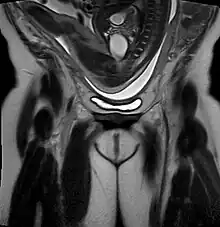

| Drawing of a frank breech from 1754 by William Smellie | |